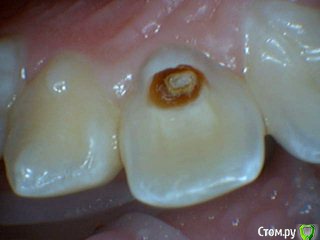

Давлетшин Опубликовано 13 июля, 2017 Поделиться Опубликовано 13 июля, 2017 Обидно понимаешь за детство, сообщений особо нет. подумать не над чем.два клинических случая. будут там пульпиты или нет? вот в чем вопрос. в одном случае пломба Витример в другом Эстелайт, без прокладок. Порядок фото несколько нарушен. Работаем над этим. Ссылка на комментарий

Давлетшин Опубликовано 13 июля, 2017 Автор Поделиться Опубликовано 13 июля, 2017 второй случай. один пациент 1 1 Ссылка на комментарий

Mikhail_29_rus Опубликовано 17 июля, 2017 Поделиться Опубликовано 17 июля, 2017 Все будет хорошо , пульпит далеко Ссылка на комментарий

Dok22 Опубликовано 28 июля, 2017 Поделиться Опубликовано 28 июля, 2017 На всякий случай рентген контроль раз в пол года пару лет и проверка на витальность. Ссылка на комментарий